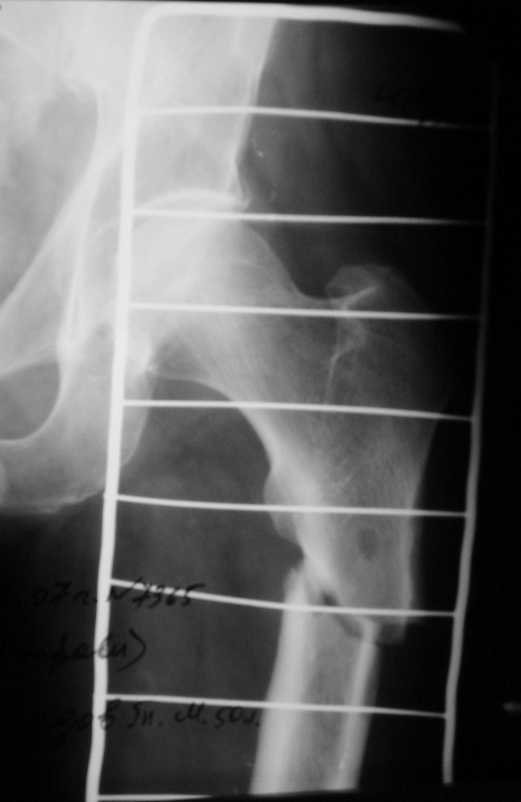

Больной М.5лет.Находится на лечении в травм. отделении по поводу патологический перелом в/3 диафиза левого бедра на фоне хронического рецидивирующего левой нижней конечности.R-снимки к сообщению.